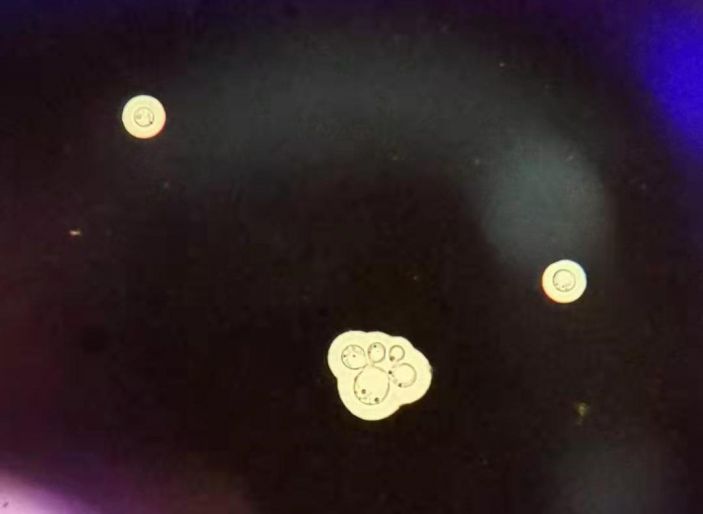

△檢驗科實驗室腦脊液培養出來的隐球菌(顯微鏡下)。

入院後迅速給予完善相關檢查。頭顱CT顯示第四腦室上方中腦導水管梗阻。随後,我院外二科(神經外科)、檢驗科緊密協作,在該名患者腦脊液中培養出新生隐球菌,終于找到了導緻其腦積水反複的元兇。莊主任分析說,患者十多年前曾因車禍緻小腦損傷,緻第四腦室上方中腦導水管畸形,再因新生隐球菌感染而發病,其患的是梗阻性腦積水并新生隐球菌性腦膜炎,患者病情危重。